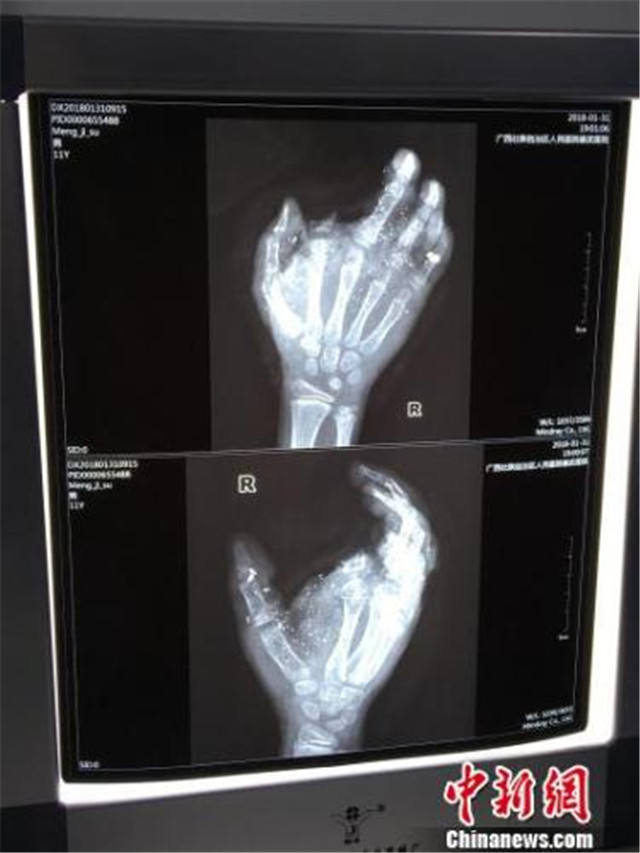

↑图为小明受伤的手掌骨骼图。

邕武医院医生兰天兵介绍,经检查发现,小明眼球有异物、肺部挫伤、右手臂和手指粉碎伤,食指断离。2月1日零点30分左右,兰天兵开始为孩子紧急做前臂皮瓣转移修复术、拇指、中指、环指再植手术,手术直至当天凌晨5点才完成。

兰天兵介绍,小明被送至南宁时,断离的食指并未一起带来。但由于断指也已经被炸得只剩一点,过于不完整,而手掌受损严重,几个手指已经无法供血,医生最终选择不接食指,抢救其他手指。兰天兵表示,目前小明的手掌已经恢复供血,有98%的痊愈率,恢复功能没有问题。